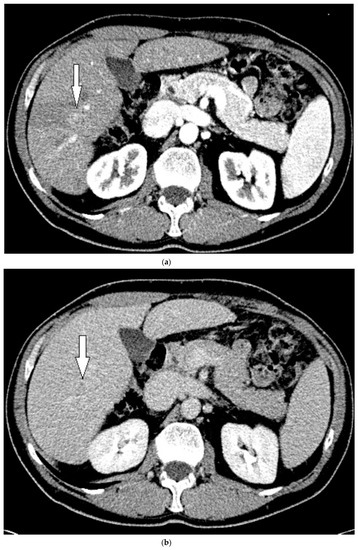

Routine US showed a heterogeneous, coarsened liver parenchyma with a suspected 2.2 cm hypoechoic structure in the right lobe on a background of geographic hepatic steatosis (Figure 1). Contrast was then administered intravenously with targeted imaging of the lesion to determine if it was focal fatty sparing or tumor. The lesion markedly enhanced (Supplementary Video S1) and began washout rapidly, and on delayed imaging, showed intense washout. It was deemed a LI-RADS M because of its early enhancement and for its marked washout (Figure 1). Given the LI-RADS M designation and for treatment planning, a four-phase CT was then approved by his health insurance company. Despite its size, the lesion was poorly visualized on the well-timed late arterial phase (Figure 2). It was equally subtle on the portal venous and 3 min phases. Knowing where the lesion was on CEUS allowed the radiologist to confirm the findings on CT, where it was deemed a LI-RADS 5 lesion. However, without the pre-existing knowledge of its presence in that location, the lesion was initially missed. The late arterial phase on the CT was bolus-triggered, which resulted in scanning occurring at 35 s post injection. Interestingly, on the CEUS, the lesion was already washing out and was iso-intense to liver by 35 s. This may explain why it was poorly seen on CT despite its intense, avid enhancement on US.

Figure 1.

Patient 1 ultrasound images, with liver lesion denoted by white arrow: (a) grayscale images showing the hypoechoic lesion. Post contrast administration ultrasound in arterial phase with matched low-mechanical-index B-mode grayscale on the right and subtraction-type post contrast images on the left (b) and delayed phase (c) of the lesion, which shows marked washout. Liver Reporting and Data System (LI-RADS M).

Patient 1 CT images using liver windows to highlight the subtle lesion easily seen on contrast-enhanced ultrasound (CEUS) (white arrow): (a) late arterial phase axial contrast-enhanced CT; (b) 3 min delayed phase.